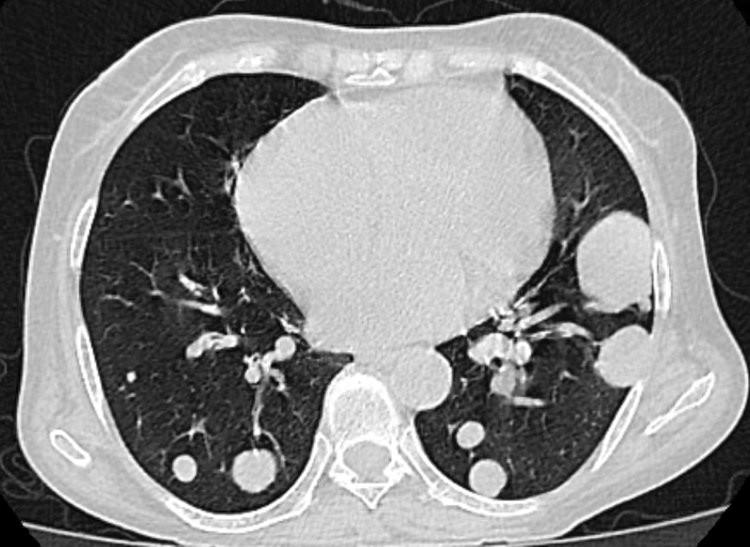

劉阿姨今年64歲,半年前因久治不愈的咳嗽去醫院檢查,在CT檢查中發現肺部有7個結節,當下醫生就判斷這些結節可能爲肺癌。這可把一家人嚇壞了,劉阿姨不抽菸不喝酒怎麼會突然罹患癌症?

• 肺結節

肺結節的發生與多種因素相關,如先天性因素、病毒/細菌/真菌感染、吸菸、石棉等,也可能是外傷或是疾病留下的痕跡。臨牀數據顯示,95%的肺結節性質爲良性,只有5%左右爲惡性結節。